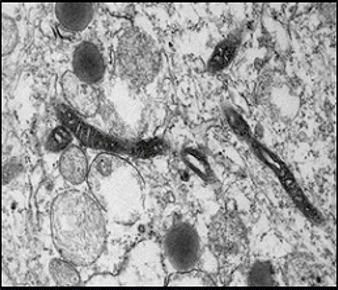

The joints of patients with inflammatory arthritis (IA) show a complex microenvironment of neoangiogenesis, immune cell and fibroblast activation leading to inflammation and joint destruction. T cells play a key role in the pathogenesis of both Rheumatoid Arthritis and Psoriatic arthritis, with differential T cell populations associated with both diseases. It has now emerged that T cell subsets can exhibit functional plasticity, particularly, making it difficult to identify discrete T cell subsets on the basis of their cytokine production. Th17 cells appear to be particularly unstable under inflammatory conditions and can become so-called ex-Th17 cells or nonclassical Th1 cells, which start to produce IFN-γ with the eventual loss of IL-17 expression. Interestingly, we have shown enrichment of polyfunctional Th1, Th17 and Ex-Th17 cells in the periphery and synovial fluid of patients with RA and PsA. In addition, the frequency of polyfunctional T cells are associated with disease activity and response to therapy, suggesting they play a key pathogenic role in disease. Regulatory T cells (Tregs) represent an important peripheral tolerance mechanism that serves to prevent autoimmunity, but fails to constrain inflammation in autoimmune diseases such as RA and PsA. Several studies examining Treg phenotype have reported a decrease in the frequency in peripheral blood of patients with RA/PsA compared with healthy control (HCs), however, studies have also demonstrated enrichment of Tregs at the site of inflammation. However, they have reduced suppressive function thus allowing pathogenic polyfunctional CD161+ cells to further potentiate inflammation. In this study, we investigated the regulation of effector T cells taken from the RA SF by Tregs. The reduced suppression was in part mediated by the CD161+ Th cells, which exhibited enhanced pathogenicity which were resistant to Treg suppression.